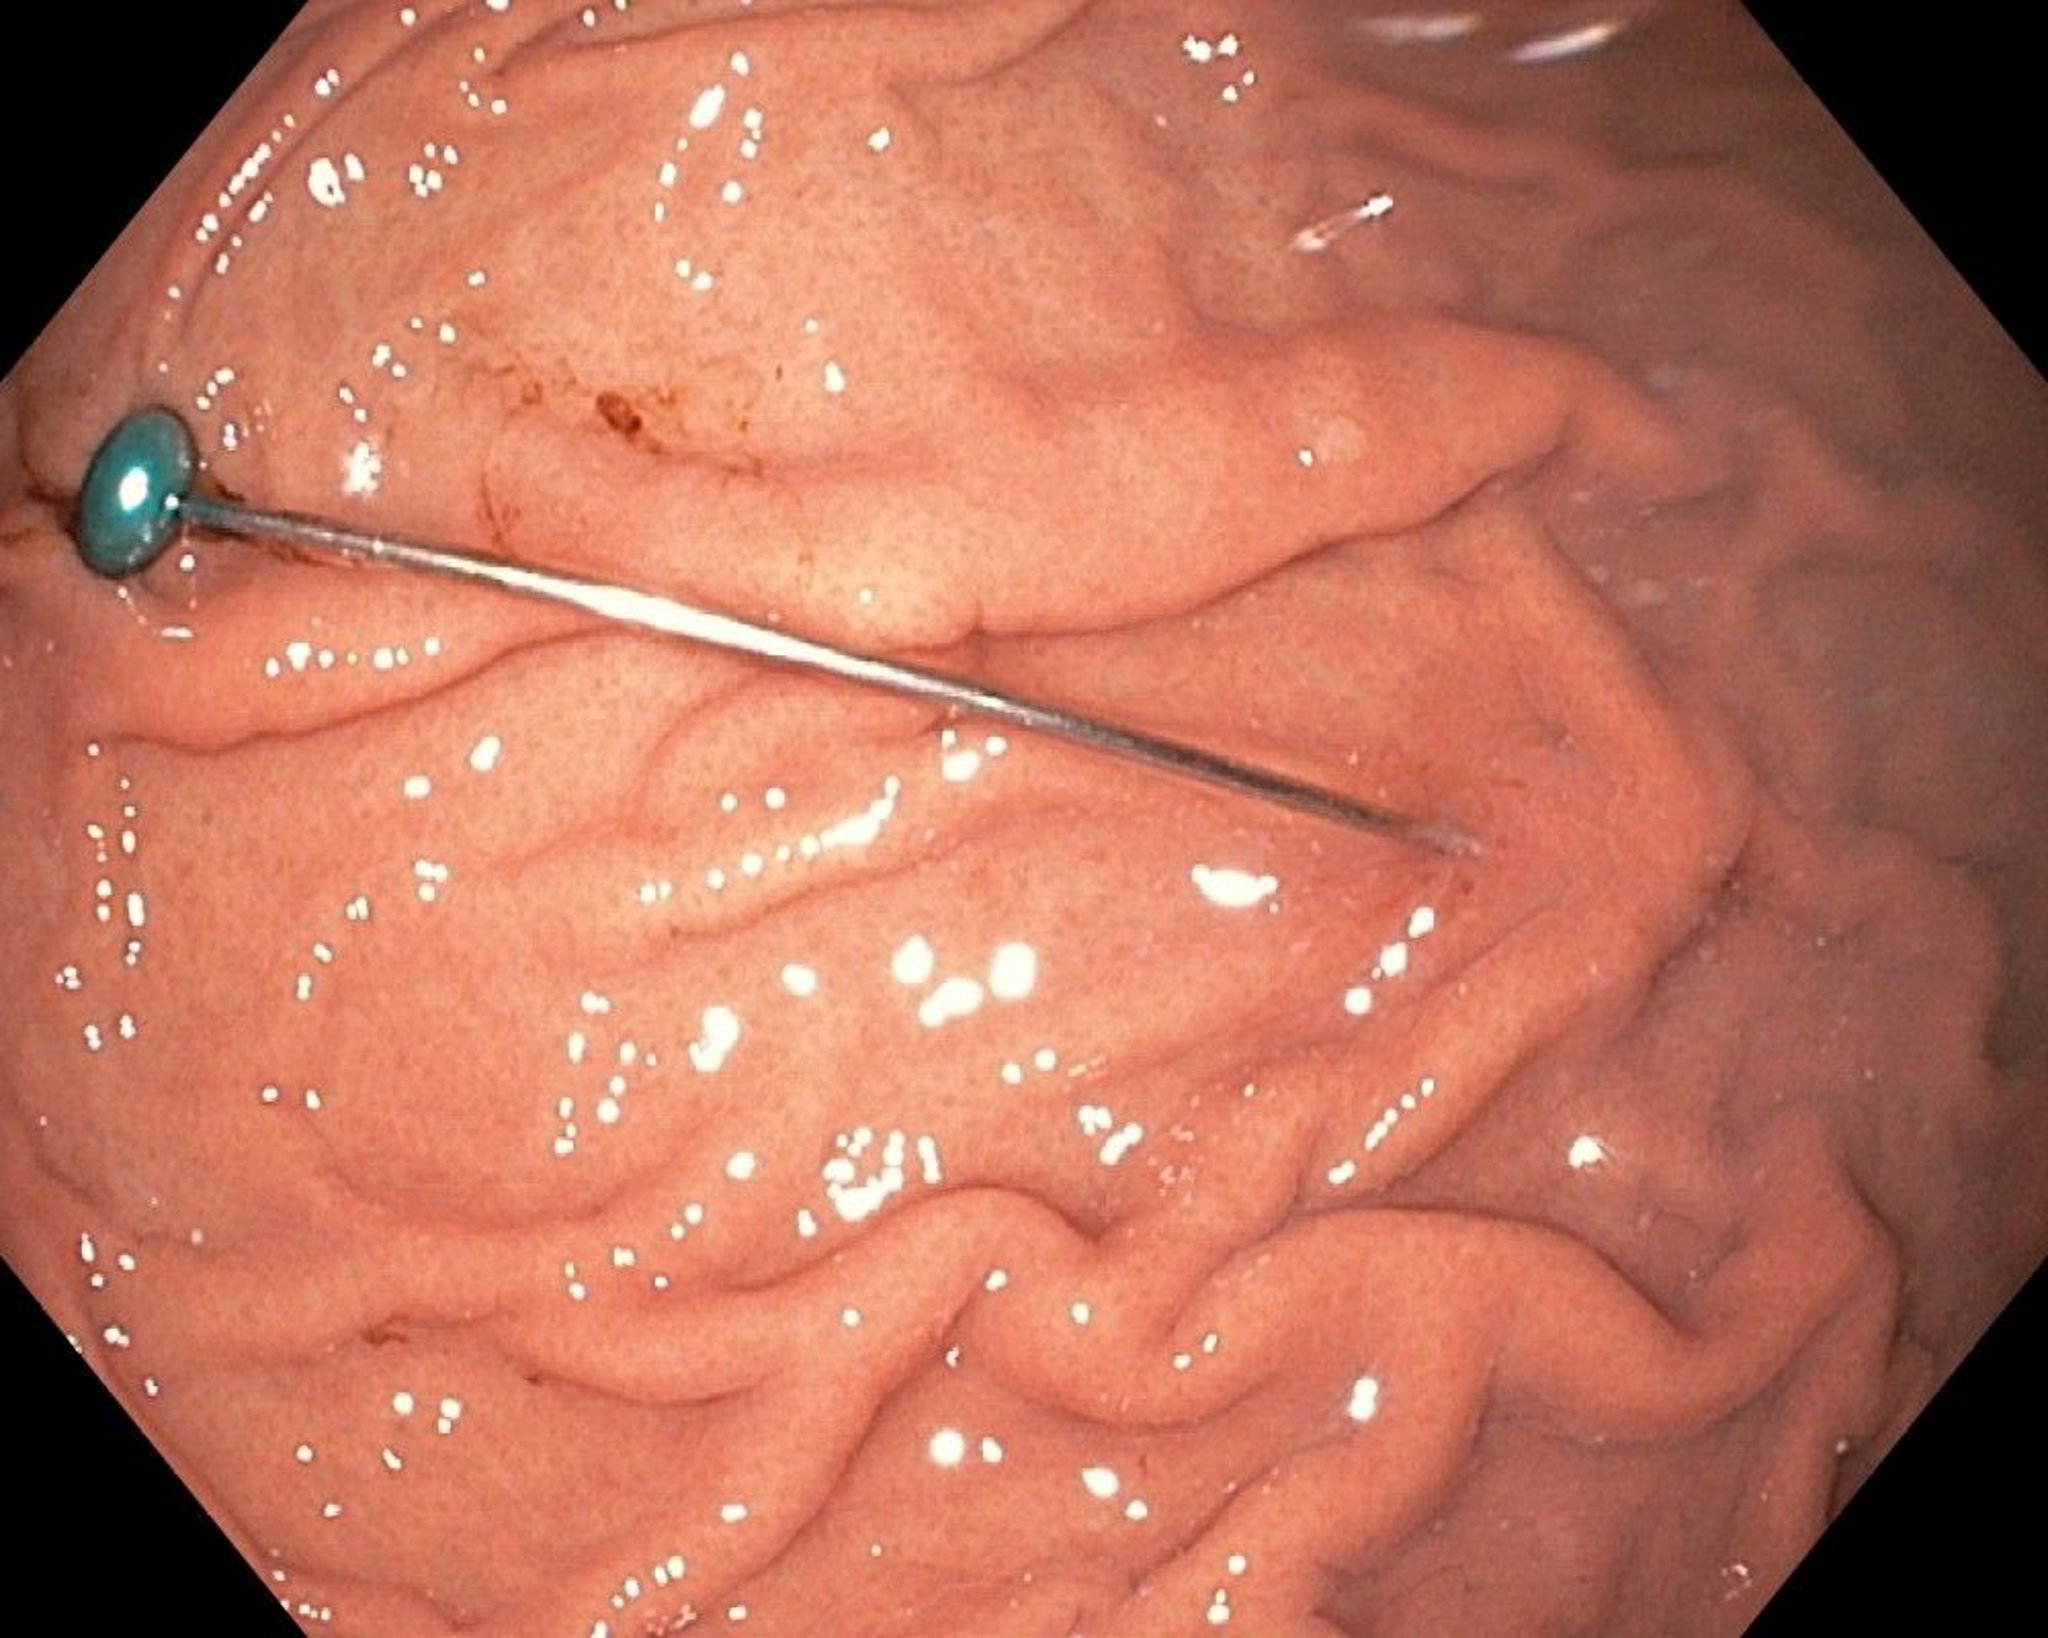

Sharp Foreign Body in the Stomach (Endoscopy)

This image shows a sharp foreign body in the stomach.

Image provided by Uday Shankar, MD.